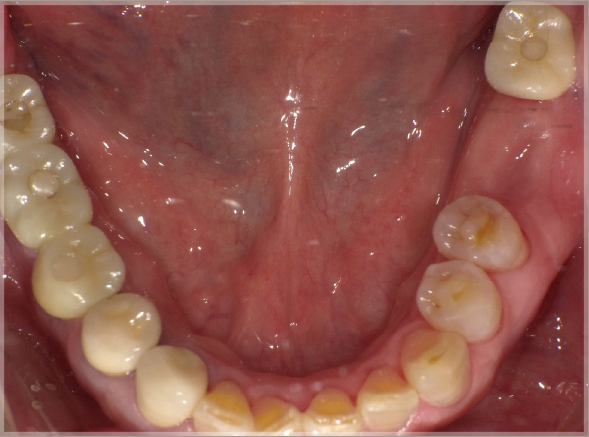

患 者 : S.K様 女性

主 訴 : 補綴物破損、義歯不適による咀嚼障害のためインプラント治療希望

初診日 : 2003年07月11日

既往歴 : 特記事項なし

1.初診時(2003年)

2.ブリッジ除去後治療用仮歯のブリッジ装着

3.治療中の仮歯(2007年)

インプラント埋入終了

4.最終補綴物装着(2008年)

5.術後14年経過(2022年)

6.術後17年経過(2025年)